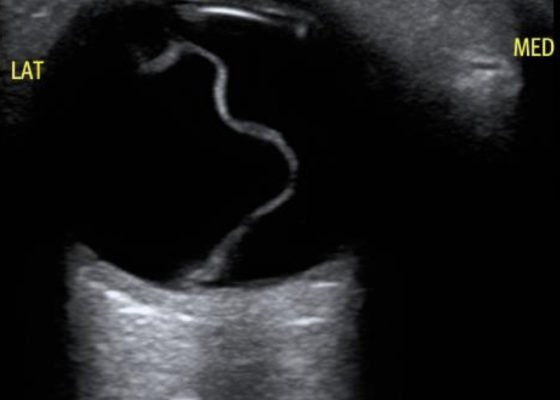

Macula-Off Retinal Detachment Identified on Bedside Ultrasound

DOI: https://doi.org/10.21980/J8WP8KPoint-of-care ultrasound was performed, demonstratinga free-floating, serpiginous, hyperechoic membrane (R) tethered at the optic nerve (ON) and ora serrata (OS), but detached at the macula (M) lateral to the optic nerve. This is diagnostic for macula-off retinal detachment. It can be differentiated from macula-on retinal detachment, in which the hyperechoic retina would appear attached posteriorly at the location of the macula just lateral to the optic nerve. Ophthalmology was consulted, agreed with the diagnosis of macula-off retinal detachment, and took the patient to the OR for laser photocoagulation.